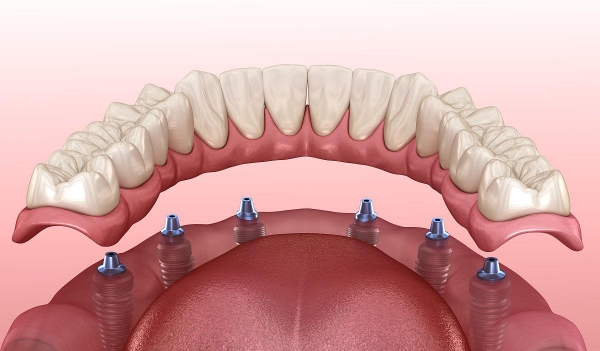

5、半口和全口種植牙費(fèi)用

半口種植牙價(jià)格一般在2萬元起,而全口種植牙價(jià)格通常在4萬元到10萬元之間。